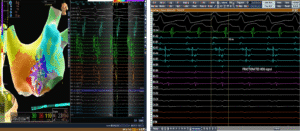

3D LAT Activation Mapping: Identifying the Circuit

LAT activation mapping demonstrated a macro re-entrant circuit in the left atrium.

Key observations:

-

Activation spanned nearly the entire tachycardia cycle length

-

High-density grid signals covered approximately 190 ms

![]()

-

The mapping confirmed a scar-related re-entry pattern

-

Propagation mapping showed wavefront circulation consistent with atypical LA flutter

In post-CABG patients, surgical scarring and atrial remodeling often create slow-conduction channels. These channels act as substrates for re-entry.

The propagation map clearly visualized wavefront movement around a scar region, confirming the arrhythmia was left atrial in origin rather than typical right atrial cavotricuspid isthmus flutter.

High-density mapping revealed:

-

Fractionated electrograms

-

Late potentials

-

Areas of low voltage consistent with atrial scar

These findings are characteristic of atypical LA flutter circuits. Fractionated signals indicate zones of slow conduction — the critical substrate maintaining re-entry.

Interestingly, the HD grid catheter mechanically “bumped” the tachycardia, leading to termination.

Despite attempts, tachycardia could not be reinduced easily, further supporting a fragile re-entrant substrate dependent on a specific conduction channel.